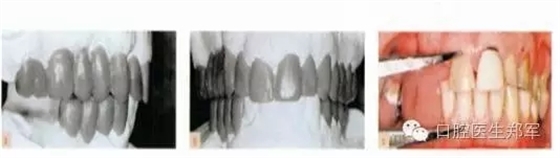

圖6 a-b 診斷蠟型 c 根據(jù)美學(xué)、生物力學(xué)和臨床冠高度的標準,設(shè)計咬合垂直距離。 |

圖7治療計劃。后牙支撐:右側(cè)種植體支持式修復(fù)的相對上下牙段、左側(cè)為縮短的牙支持式修復(fù)的牙弓。少量增加咬合垂直距離,在前牙設(shè)計非正中引導(dǎo)和左右尖牙引導(dǎo)。 |